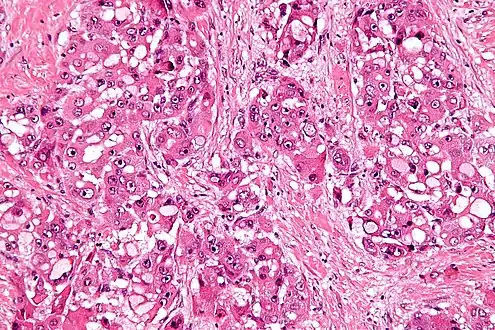

Intermed. mag.

High mag.

The histopathology of FLC is characterized by laminated fibrous layers, interspersed between the tumor cells. Cytologically, the tumor cells have a low nuclear to cytoplasmic ratio with abundant eosinophilic cytoplasm.[1] Tumors are non-encapsulated, but well circumscribed, when compared to conventional HCC (which typically has an invasive border).